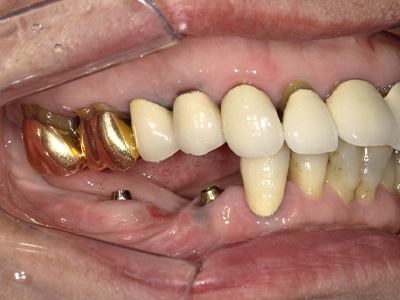

複数の歯がない場合には、

オールオン4、

インプラント

オーバーデンチャーを

検討します

オールオン4

上顎または下顎すべてを4本または6本のインプラントで固定する治療法です。顎の骨が少ない方でも手術可能で、インプラントでしっかりと固定できるためずれたり、外れたりすることが無く噛むことができます。治療費や身体への負担が少ないというメリットがあります。

オーバーデンチャー片顎に2~6本のインプラントを埋入し、アタッチメントを取り付けて入れ歯を固定します。インプラントが固定源となるため、通常の入れ歯よりも安定し、「噛みやすい・フィットする・痛くない」を実現します。すべての歯にインプラントを埋入するよりも、身体的・経済的負担が少ないのも特長です。